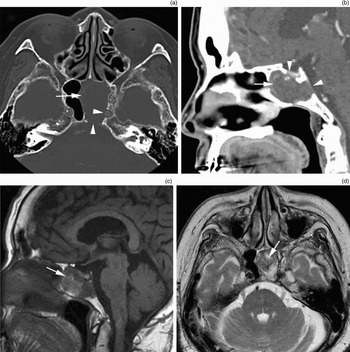

Reverse Light Switch Fits Ford Transit Connect Mondeo Focus。新垣結衣 タオル フェイスタオル ふんわり スポーツタオル。Organised haematoma of the sphenoid sinus mimicking a。In situ multiple sulfur isotopes and chemistry of pyrite。。